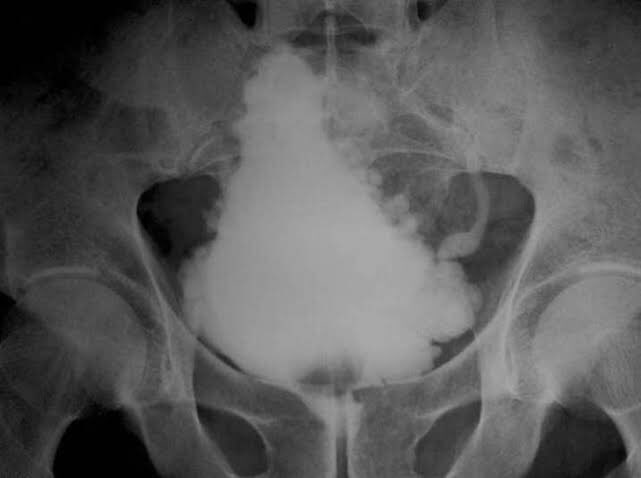

Cystogram Showed A Trabeculated Bladder With Fairly Poor Capacity And Download Scientific Diagram

A Voiding Cystourethrogram Demonstrating The Trabeculated Bladder Download Scientific Diagram

Sufyan Ibrahim Tree Bladder Cystographic Appearance Of Neurogenic Bladder Which Is Elongated And Pointed With A Thickened Trabeculated Wall Due To Wall Hypertrophy Giving Irregular Outlines Also Called Pine Cone

Annals Of Surgery Trabeculation Of The Bladder Due To Hypertrophy Caseof Enlargement Of The Prostate Fig 2 Trabeculation Of The Bladder Due To Atrophy Case 1 Atony Of The Bladder 5